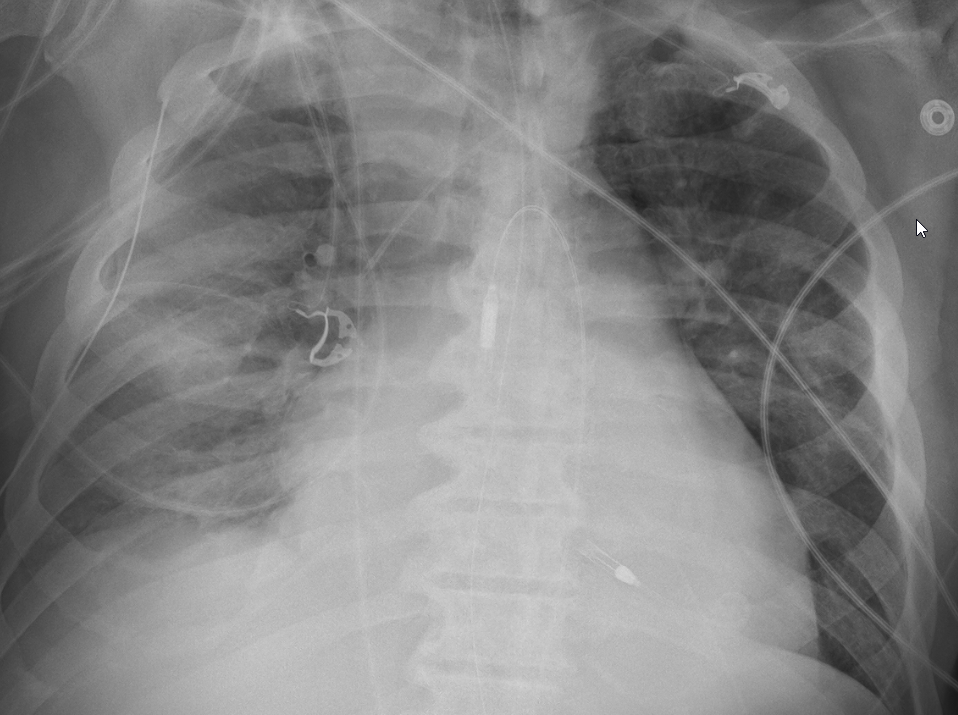

ICU (evolving) stories: A young patient was admitted with "aspiration pneumonia" a few days ago. On...

ICU (evolving) stories: A young patient was admitted with "aspiration pneumonia" a few days ago. On mechanical ventilation. Afebrile. Negative cultures. CXR when you first see him...